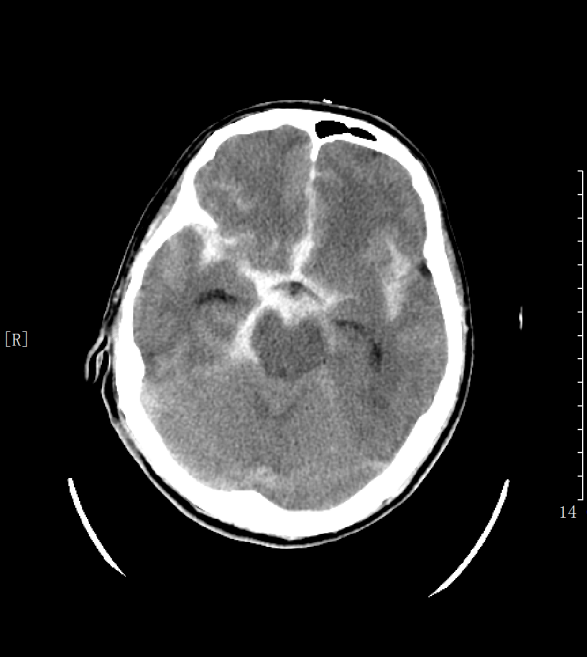

孫先生的家人發(fā)現(xiàn)后速將他送到當(dāng)?shù)蒯t(yī)院做檢查,頭顱CT提示蛛網(wǎng)膜下腔出血,顱腦CTA顯示為顱內(nèi)多發(fā)動脈瘤(共2個)!醫(yī)生擔(dān)心動脈瘤還有隨時破裂的風(fēng)險,建議孫先生盡快手術(shù)治療。

CT檢查(蛛網(wǎng)膜下腔出血)

患者入院后,頭顱CT血管造影檢查提示:腦內(nèi)多發(fā)動脈瘤并破裂。